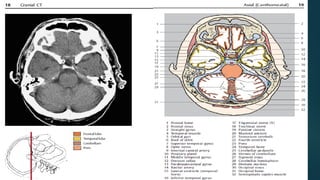

Este documento es el programa para un taller de imágenes del curso de emergencia 2015 impartido por el Dr. Víctor Delgado. El taller se centra en el uso de imágenes médicas para el diagnóstico y tratamiento de pacientes en coma traumático según la base de datos de Marshall. El Dr. Delgado es el único instructor repetido a lo largo del documento.